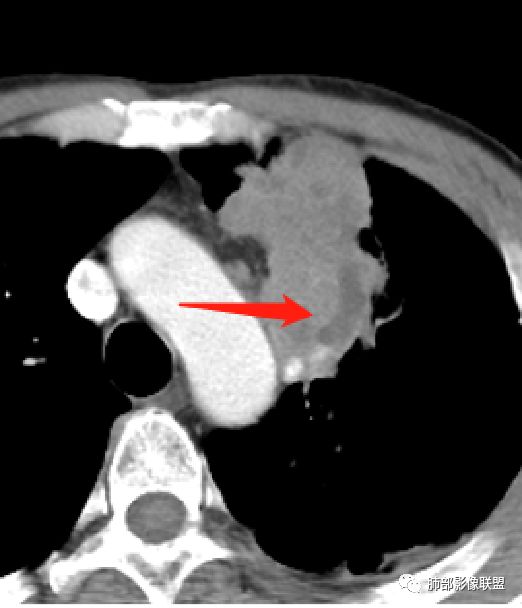

1.左肺上叶尖后段体积变化不大,病灶长轴沿支气管血管束向肺门侧生长,

2.病灶外围大,内带小,外朝内蔓延

3.病灶边缘以收缩为主,局部稍膨隆,

4.病灶整体轻中度强化,强化较均匀,局部见多个管状低密度影,边界清,考虑支气管粘液栓;病灶局部可小灶样的低密度区,未见强化,考虑坏死灶,坏死灶周围见明显强化的壁,壁清楚、光整,未见中断,倾向炎性肉芽肿的坏死;

5.病灶内血管部分走形自然,部分走形僵直、粗细不均,提示病灶有部分破坏力,但是不强;

6.病灶与纵隔胸膜呈“糊墙”样改变,倾向炎性病灶;

6.纵隔淋巴结肿大,密度均匀,强化均匀;